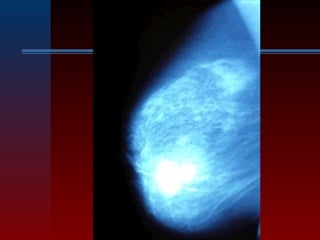

 MAMOGRAFIA

– Es la más usada, se hacen dos proyecciones:

craneo-caudal y lateral

– Del 10 al 50 % de los cánceres detectados por

mamografía no son palpables.

– Hay tumores palpables que no dan imágenes

mamográficas en un 10-20 % casos

– No es útil para pacientes <30 años

– Se usa como screening desde los 40

– Sólo el 25 % de las lesiones mamográficas no

palpables son malignas

– Las áreas espiculadas y densas, de bordes mal

definidos, suelen ser cánceres.

– Lesiones dudosas, que suelen requerir biopsia,

son las microcalcificaciones, asimetrías

ductales, distorsión de la arquitectura glandular,

retracción del pezón o de la piel.

 La mamografía puede detectar entre 80

a 90 por ciento de los tumores que no

pueden ser palpados sino hasta 2 años

después.

 En las mujeres jóvenes, la mamografía

no es un método efectivo para

detección del cáncer. Los rayos-x de la

mamografía no pueden penetrar el

tejido glandular de los pechos de las

mujeres jóvenes, porque es muy denso,

esto hace que los resultados no sean

exactos.